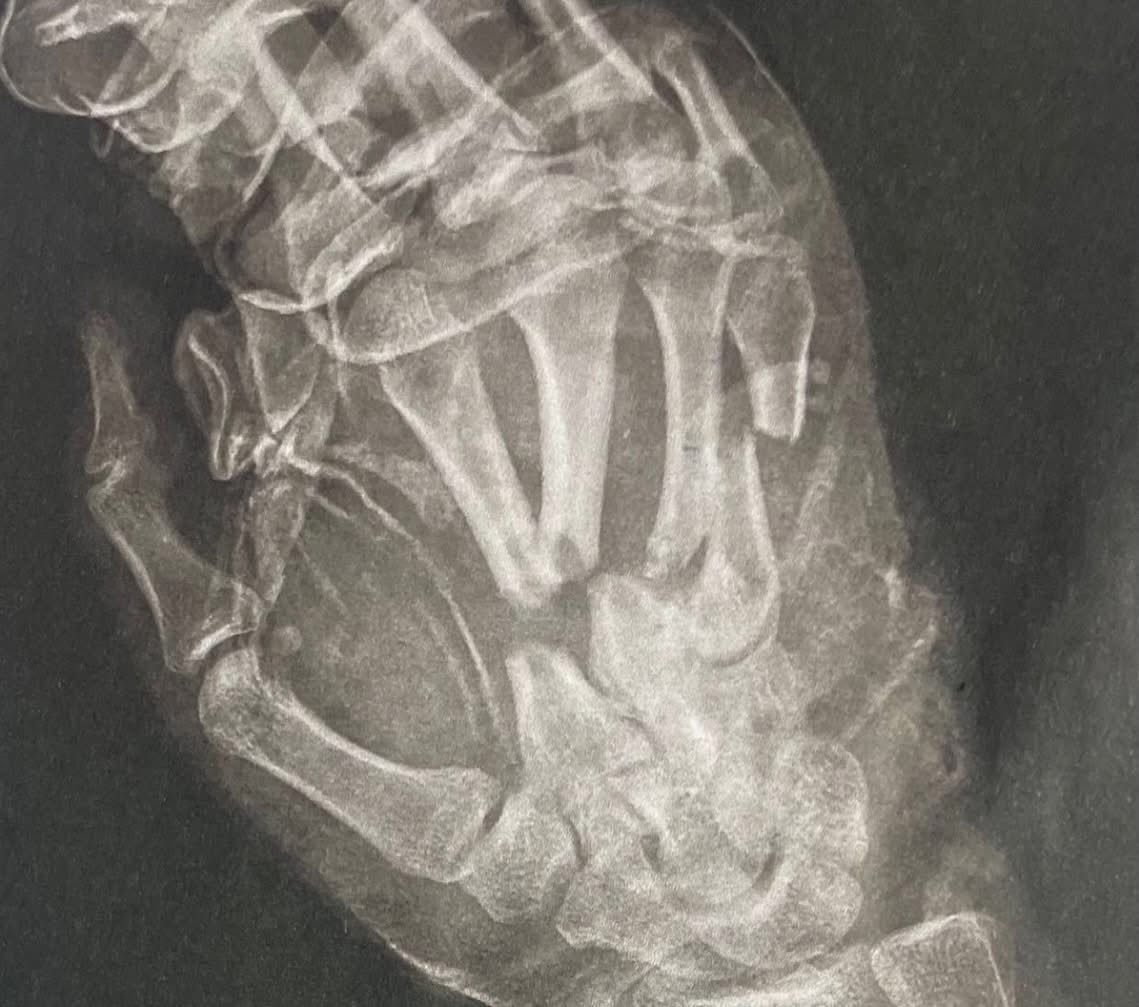

• остеосинтез спицями другого-п’ятого пальців,

У післяопераційному періоді важливу роль у відновленні відіграла гірудотерапія — лікування п’явками. Така терапія сприяє покращенню кровообігу, зменшенню набряку та розсмоктуванню гематом.

Основна мета лікування — збереження кисті та її функцій у молодого пацієнта.